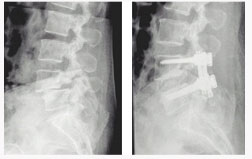

후외방 유합술(Posterlateral fusion) : 광범위한 후방 감압술 후 척추 외측에 있는 후관절과 횡돌기 간의 유합을 얻는 것.

- 충분한 감압을 얻을 수 있다.

- 신경 손상의 위험이 적다